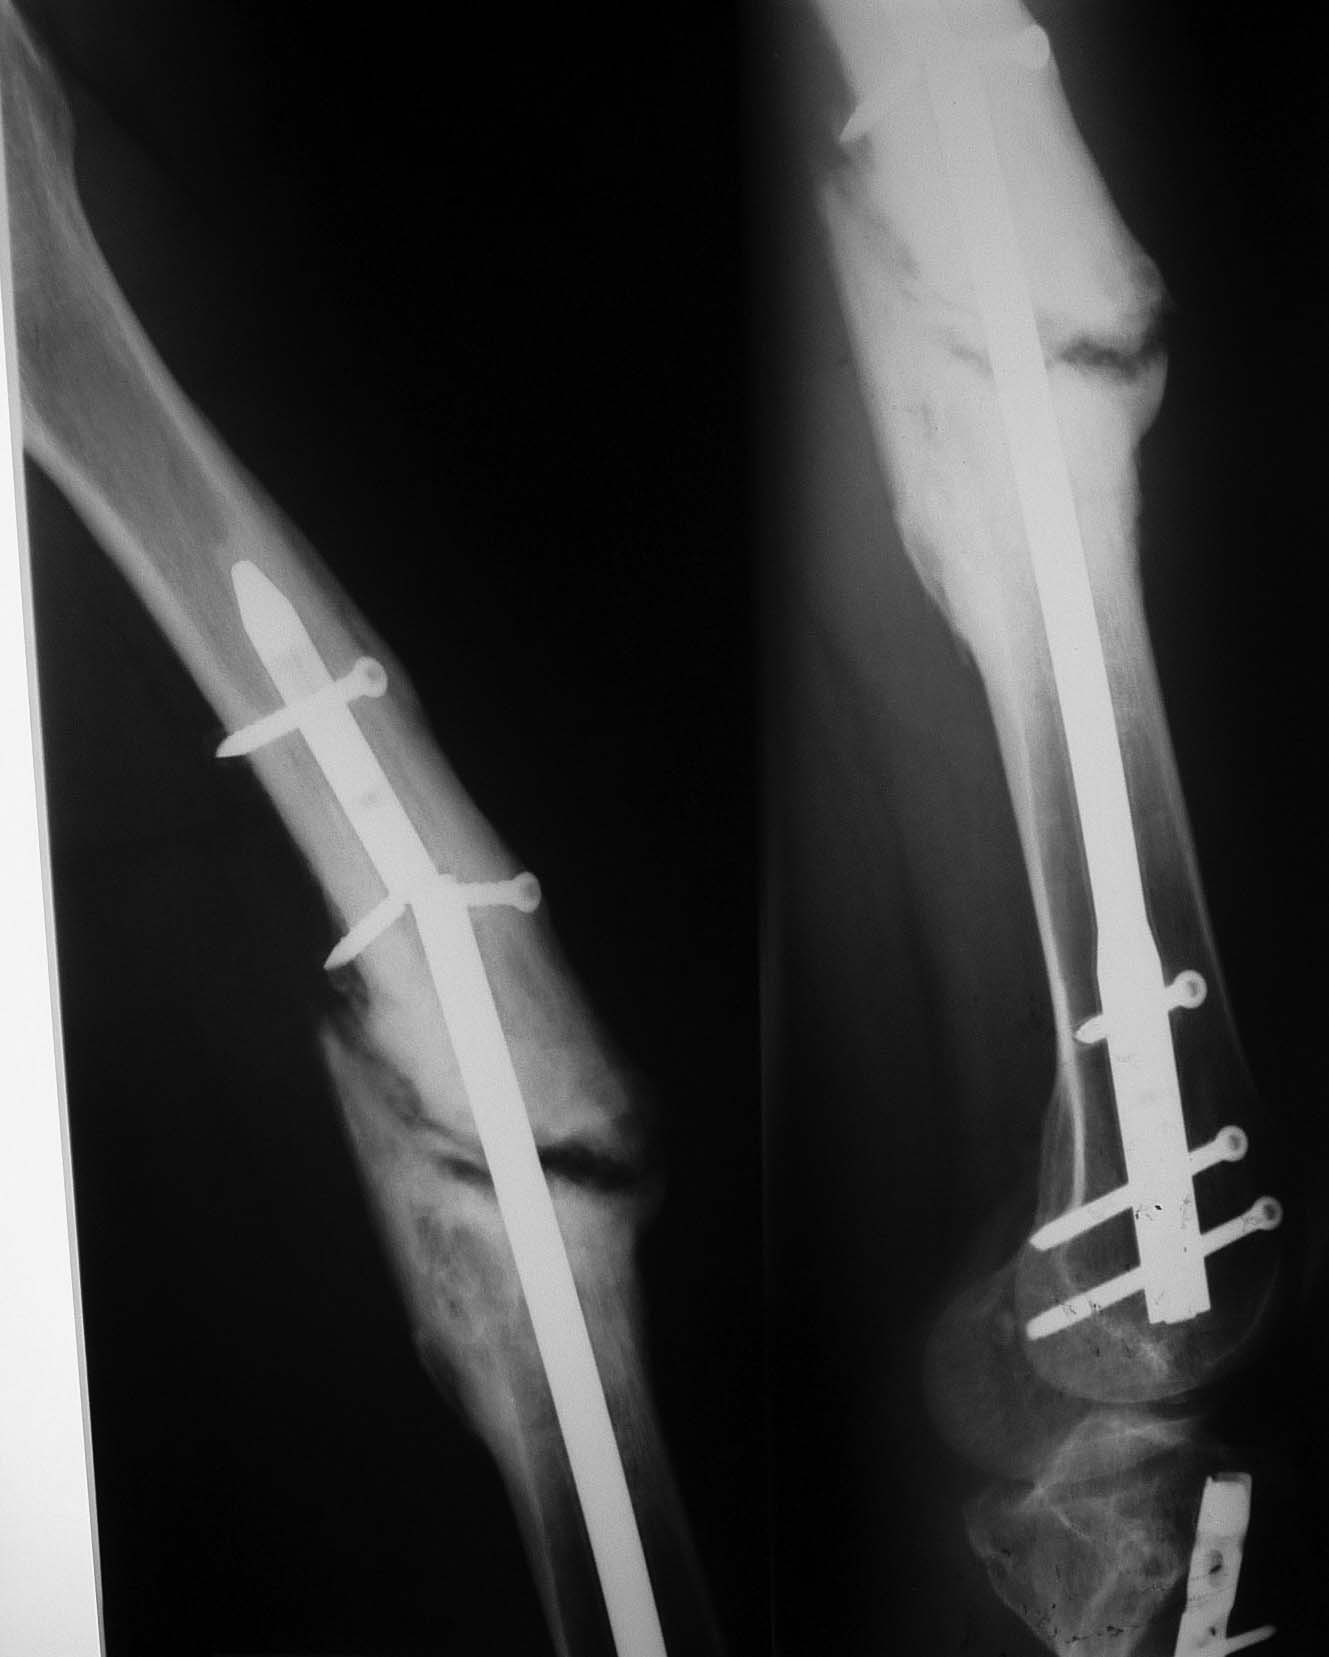

У Синтеза есть хороший набор для этих целей. С возможностью охлаждения формируемого канала и забора аутостружки. Вариант не очень бюджетный и развертки достаточно агрессивные. Нужен постоянный контроль, чтобы не пенетрировать кортикальный слой. Во вложении пример. Правда тоже не голени, а верхней 1\2 бедра (снимки до и через 3 мес после операции).